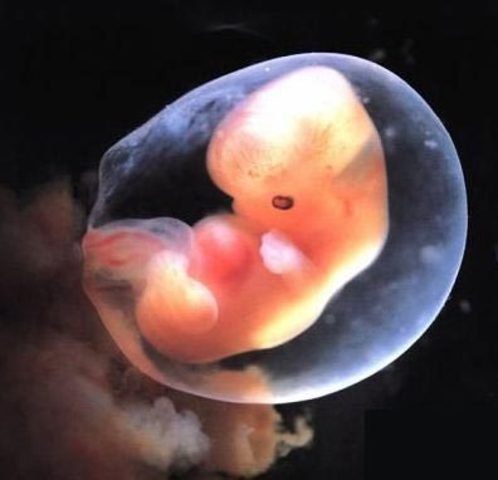

9 Weeks Pregnant

The baby is now about the size of a grape. All of the baby's body parts are formed and will continue to grow. The baby's teeth will begin to form over the next few weeks. Her eyes are fully formed. Event though her eyes are fully formed the eye lids are fused shut and will not open until 27 weeks. The baby's earlobes, nose, adn mouth are fully distinct now. The baby still weighs about a fraction of an ounce. In this week the baby is considered to be a embryo.